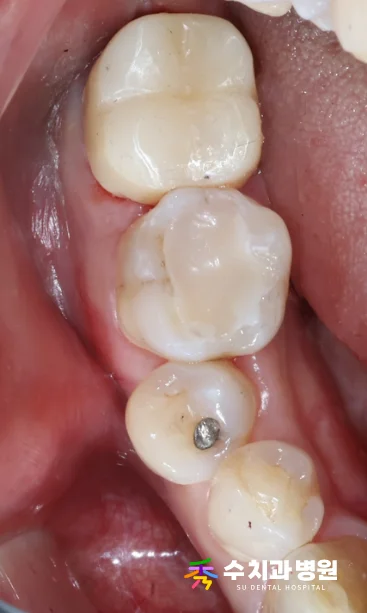

[📸 치료 후 사진] (촬영일: 2025년 9월)

자연치아와 매우 유사하게 심미성이 회복되었으며,

안정적인 교합 상태를 확인하며 치료를 마쳤습니다.

현재 환자분은 불편함 없이 편안하게 식사 중이십니다.